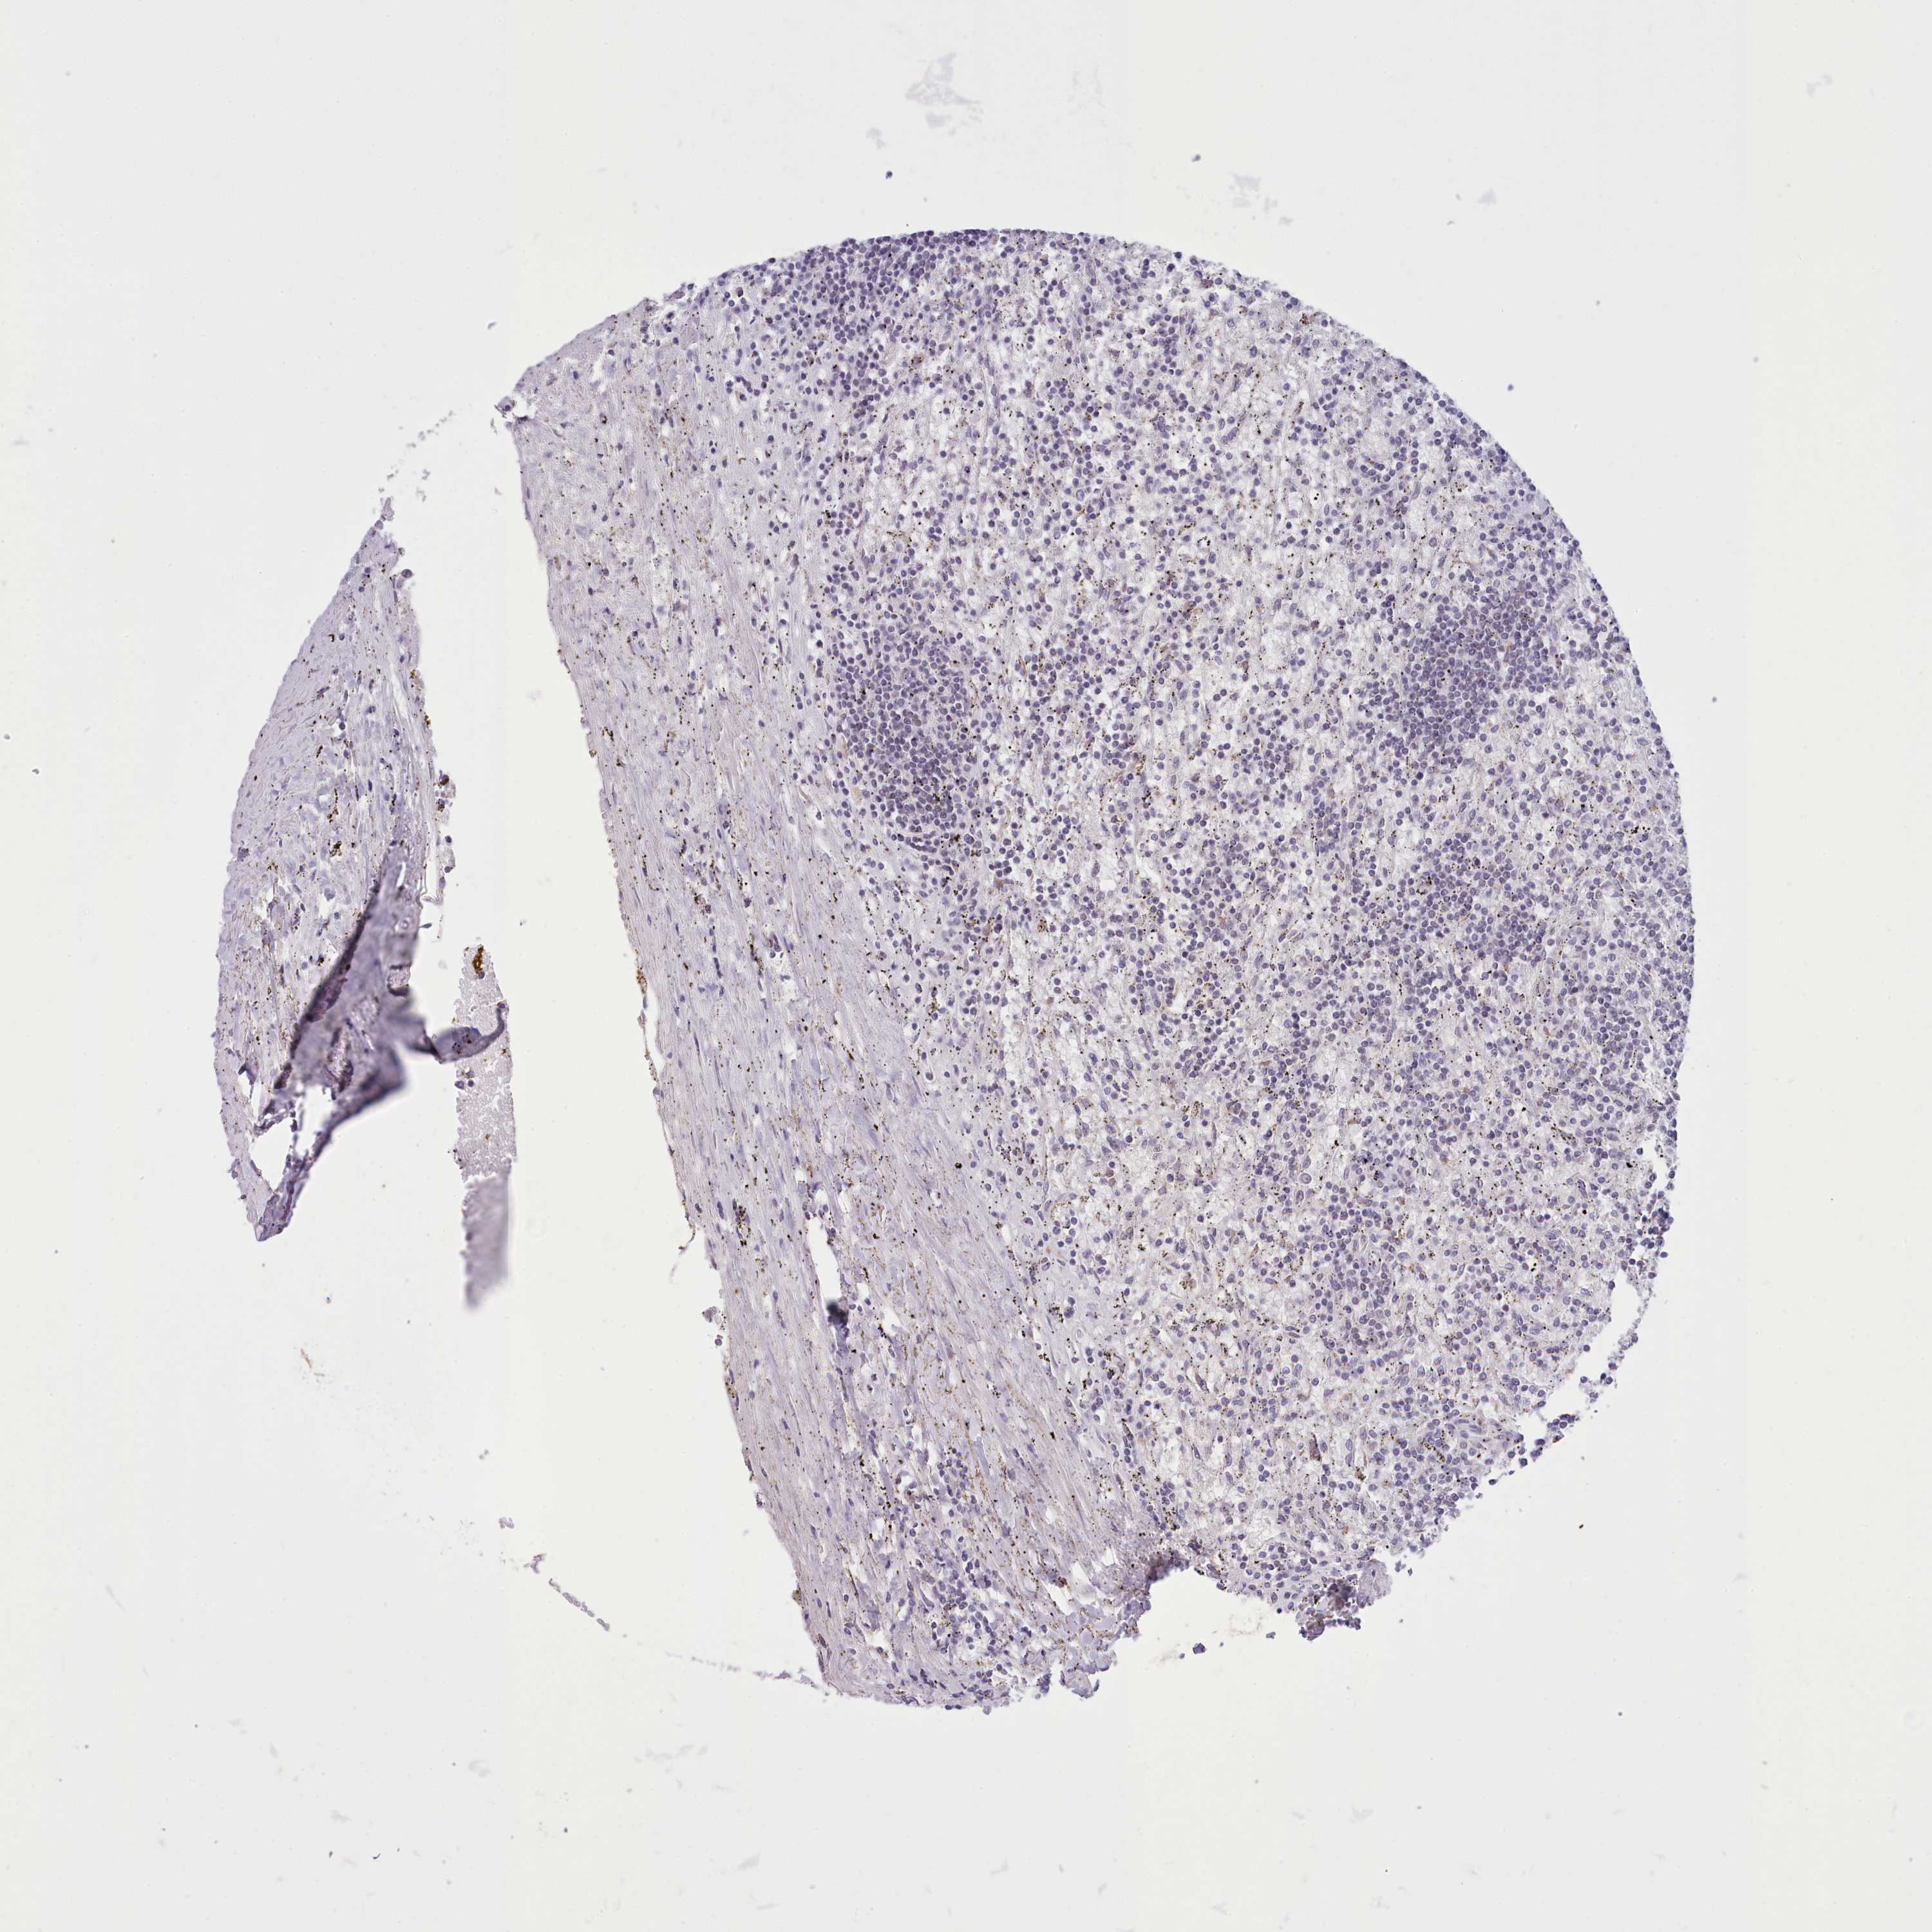

CANCER LYMPHOMA Show tissue menu

LYMPHOMA - Protein expressioni

A mouse-over function shows sample information and annotation data. Click on an image to view it in a full screen mode. Samples can be filtered based on level of antibody staining by selecting one or several of the following categories: high, medium, low and not detected. The assay and annotation is described here.

Each image is clickable and will lead to virtual microscopy that enables deeper exploration of all samples and also displays staining intensity scores, fraction scores and subcellular localization as well as patient and tissue information for each sample.

Antibody HPA048722

Hodgkin's disease, NOS

Malignant lymphoma, non-Hodgkin's type, High grade

Malignant lymphoma, non-Hodgkin's type, Low grade